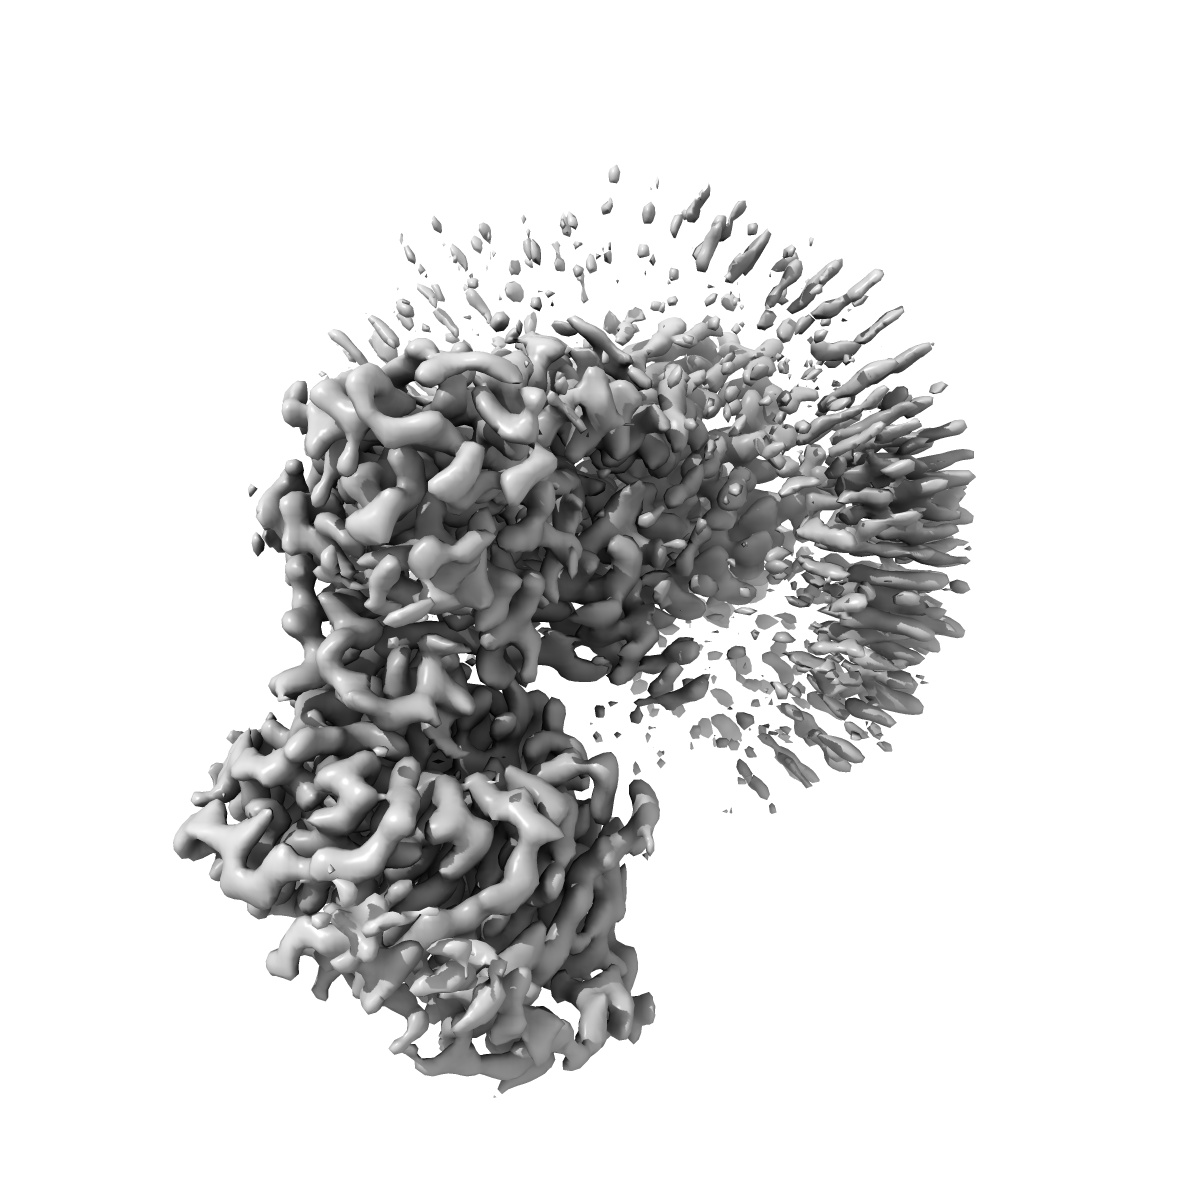

Cryo-EM structure of the human adenosine A1 receptor-Gi2-protein complex bound to its endogenous agonist and an allosteric ligand

Single-particle3.2 Å

Sample: Human adenosine A1 receptor-Gi2-protein complex bound to its endogenous agonist adenosine